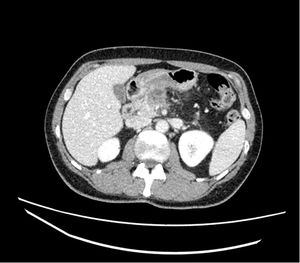

Posoperatorio inmediato y análisis anatomopatológico. El posoperatorio transcurrió sin incidencias, se realizó un TC abdominal de control a los cinco días (fig. 8), y fue dado de alta el día 7 posoperatorio sin complicaciones. El análisis anatomopatológico evidenció un adenocarcinoma pancreático de 2,5cms de diámetro invasión vascular de vaso de pequeño calibre e invasión de la capa adventicia de la VMS, márgenes venosos y quirúrgicos libres; sin infiltración perineural, 0 ganglios afectos de 30 analizados, ypT1ypN0 R0 (UICC8aEd), grado regresión GRT 2 (respuesta parcial), Grado regresión Evans GIIa.